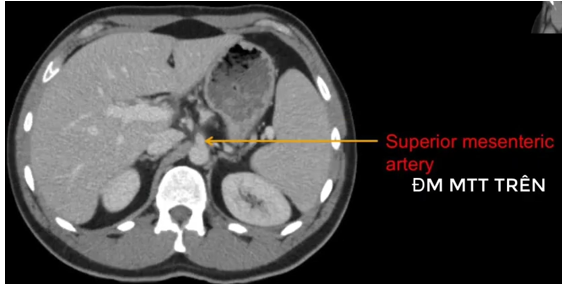

đm thận T?